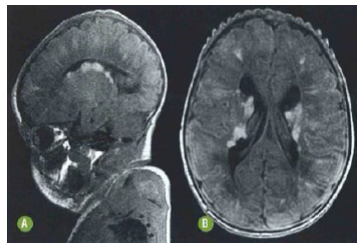

A seguinte ressonância magnética encefálica

de neonato corrobora para o diagnóstico de

esclerose tuberosa, tendo como principal

achado